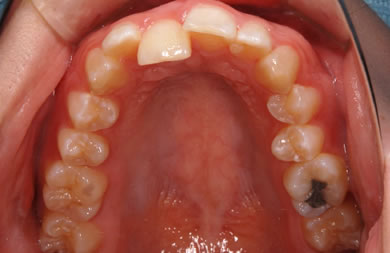

| 性別/年齢 | 女性 / 19歳 | ||||||||||||||||||||||||||||||||

| 主訴 | 上のデコボコの歯を綺麗にしたい。 | ||||||||||||||||||||||||||||||||

| 治療方針 | 上顎の歯の傾斜を正常に治す事で下顎を正常な位置に推進させ、非抜歯にて治療を行う。また、上下の顎のずれの治療のため、装置にゴムを使用し審美的・機能的に良い咬合を獲得させる。 | ||||||||||||||||||||||||||||||||

| 治療内容 | 唇側矯正(シルバー) | ||||||||||||||||||||||||||||||||

| 総治療費 | 659,300円 | ||||||||||||||||||||||||||||||||

| 治療期間 | 1年9ヶ月 |